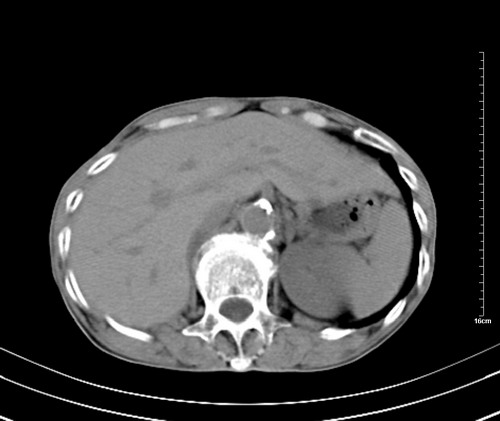

病人,女,79岁,主要因腹疼二月入院,彩超,肝,胆,脾,未见异常,胸透上消化道造影未见异常,化验白细胞增高,内科医生让做胸部ct检查,因为熟人多做了腹部(外科会诊考虑胆囊炎).现ct片如下请假各位战友.

1 气管旁、隆突下淋巴结明显肿大,肝左叶外侧段低密影,都考虑转移。

2 肝右后叶下段明显增大,片状低密影,但因各种伪影显示不佳,不排除病变。

后中纵隔团块影,伴气管、食道受压移位,首先考虑转移瘤,肝s5段低密度灶。建议增强检查,另外其结肠是否有问题请提供,右肺部分肺叶局限含气增多,考虑局限肺气肿。

后中纵隔团块影,伴气管、食道受压移位,首先考虑转移瘤,肝表现同11773。